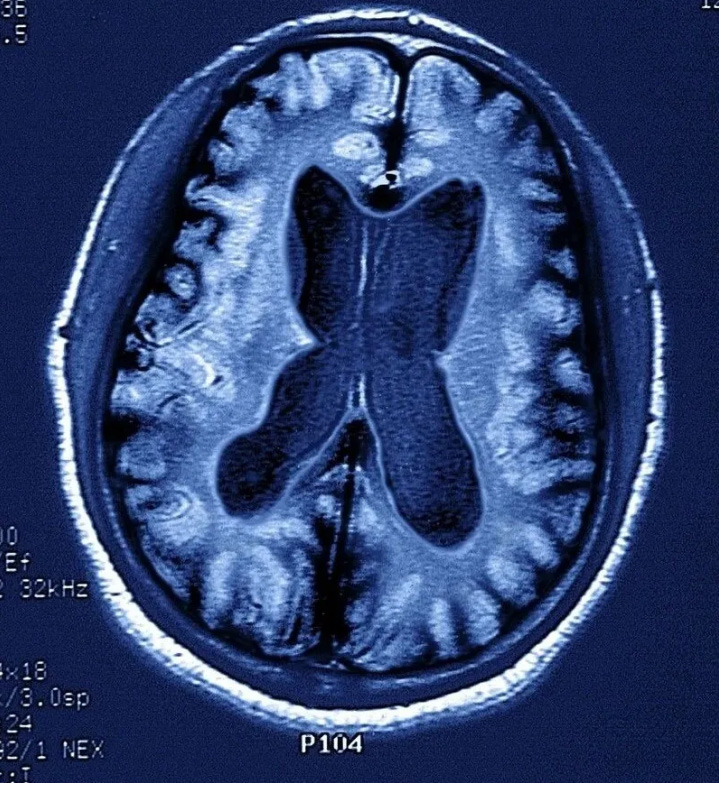

一般來說,記憶力下降是失智癥的核心癥狀,但它不是診斷失智癥的充分條件,目前臨床上診斷失智癥還要結(jié)合其它手段,如一系列的量表評估,MRI等客觀檢查。

因而當(dāng)記憶出現(xiàn)問題時,可就診于各大醫(yī)院神經(jīng)內(nèi)科記憶門診,完成一系列的神經(jīng)心理學(xué)量表測試、抽血檢查(查APOE ε基因型等)、腰穿腦脊液檢查(Aβ1-42的檢測)、尿和便標(biāo)本、普通頭顱核磁,如有必要還需做PET-MRI以檢測腦內(nèi)淀粉樣蛋白沉積。通過上述的綜合測試評估病情,給予診療意見。